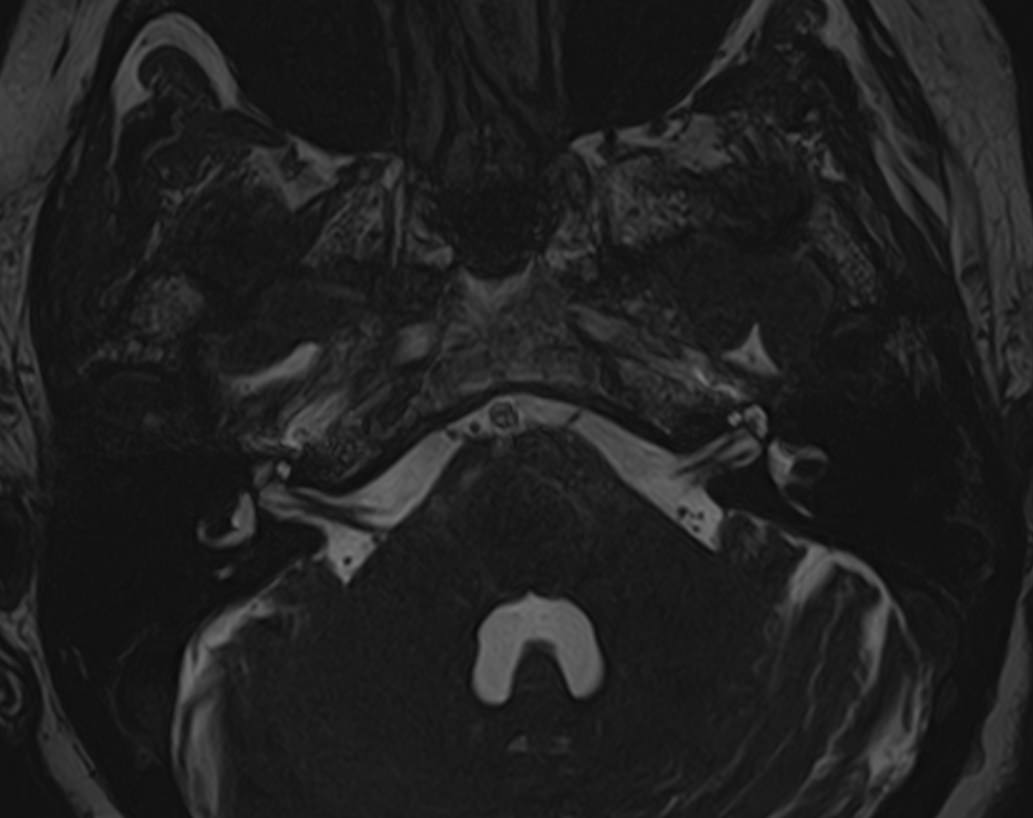

Мосто-мозжечковый угол — это пространство вблизи основания черепа в виде углубления между анатомическими образованиями: продолговатым мозгом, мозжечком и Варолиевым мостом. В этой области располагаются волокна многих черепно-мозговых нервов (например, лицевого, тройничного, преддверно-улиткового), проходят мозговые артерии и многочисленные вены мозжечка.

В мосто-мозжечковом угле часто развиваются воспалительные процессы (арахноидиты) с формированием в дальнейшем арахноидальных кист. Могут выявляться аневризмы расположенных здесь артерий. Но чаще всего в этой области образуются объемные образования, как злокачественные, так и доброкачественные, которые сдавливают расположенные там нервные волокна, кровеносные сосуды и пути ликворного оттока. Наиболее часто встречающаяся опухоль этой области — невринома преддверно-улиткового нерва. В большинстве случаев она имеет доброкачественный характер, развивается, как правило, у людей трудоспособного возраста, преимущественно у женщин. Реже встречаются менингиомы и холестеатомы мосто-мозжечкового угла.

Самым информативным, при этом быстрым и безопасным, методом диагностики опухолей мосто-мозжечкового угла на сегодняшний день является магнитно-резонансная томография с контрастированием. В клинике «Доступная медицина» проводится эффективная диагностика патологии мосто-мозжечкового угла с использованием новейшего томографа TOSHIBA VANTAGE TITAN 1,5 Тесла. Высокая мощность магнитного поля 1,5 Тесла позволяет получить подробное изображение этой труднодоступной для диагностики области в различных плоскостях.

Контрастирование проводится контрастным веществом на основе солей гадолиния (химический элемент, относящийся к редкоземельным металлам). Применяемый контрастный препарат накапливается в патологическом очаге, за счет чего при сканировании усиливается его яркость изображения. Это дает возможность выявить опухоли малых размеров (до 3 мм) и назначить своевременное лечение. Кроме того, контраст заполняет просвет сосудов, благодаря чему на снимках появляется детальное изображение сосудистой сети. Это позволяет диагностировать патологическую извитость, аневризмы, мальформации, при вазоневральном конфликте — зоны сдавления черепно-мозгового нерва кровеносным сосудом.